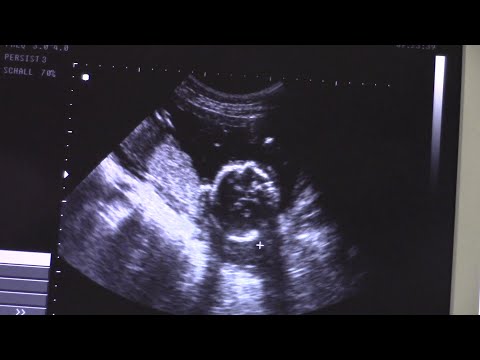

УЗИ плода на 21 недели беременности.